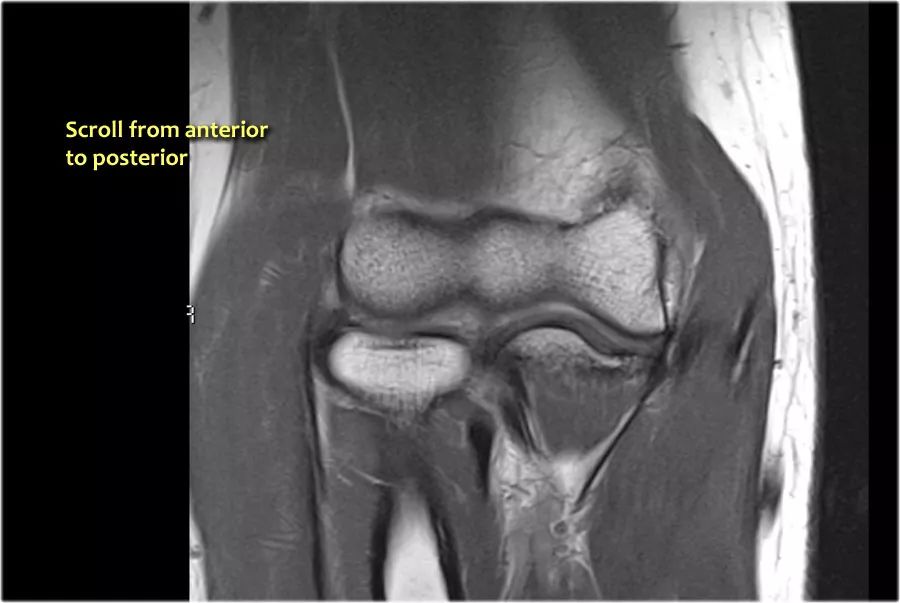

我们可以从连续的冠状位MRI图像观察。

常见的伸肌腱起源于外上髁。在T1W图像上,肌腱应具有低信号强度(黄色箭头)。